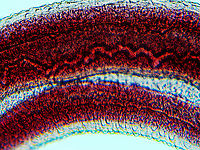

Blood Fluke (Male) - Schistosoma mansoni

''Schistosoma mansoni'' is a water-borne parasite of humans, and belongs to the group of blood flukes. The adult lives in the blood vessels near the human intestine. It causes intestinal schistosomiasis. Clinical symptoms are caused by the eggs.